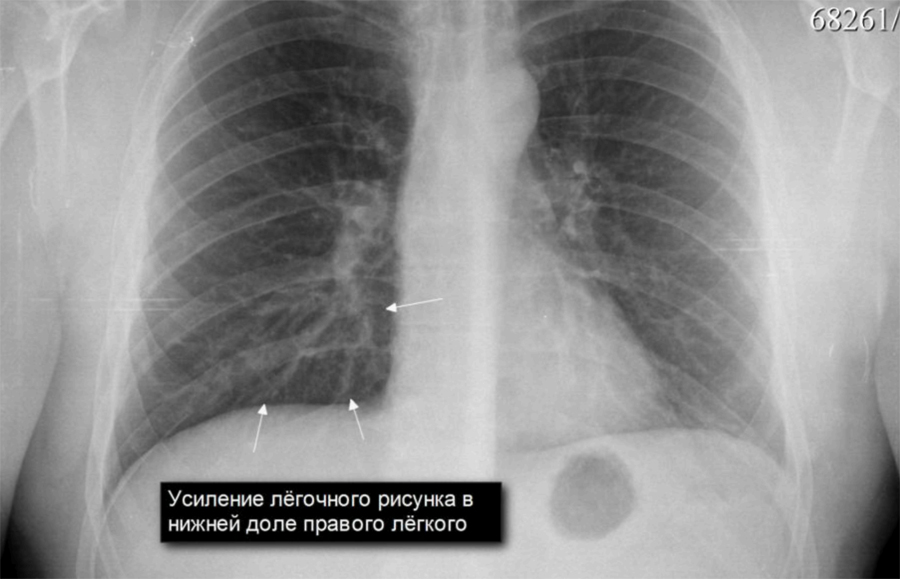

Ячеистая деформация легочного рисунка: медицинская визуализация